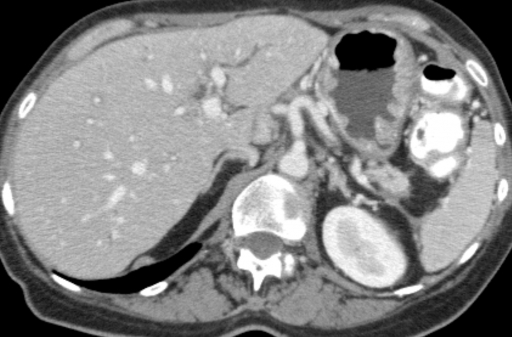

Фотографии и изображения, связанные с симптомами первичного склерозирующего холангита